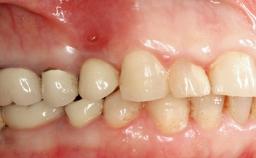

Peri-implant Carcinoma

Oral implants are highly successful and offer long-term benefits, especially in the rehabilitation of edentulous patients or patients with oral defects following ablative tumor surgery (Albrektsson and coworkers 1986), and also after radiation therapy (Schiegnitz and coworkers 2014). With the number of implants placed globally going into the millions, implant dentists have observed some rare adverse events. Although carcinogenesis around implants is an exceedingly rare phenomenon, we recently reported about 15 patients treated for carcinomas adjacent to implants at our clinical department over a period of fifteen years (Moergel and coworkers 2014). The following case represents a patient of this cohort; it discusses possible risk factors and makes suggestions for a recall schedule. A 70-year-old woman was referred to our outpatient department for evaluation of a rapidly growing macroscopic alteration of the mucosa in the left mandible.